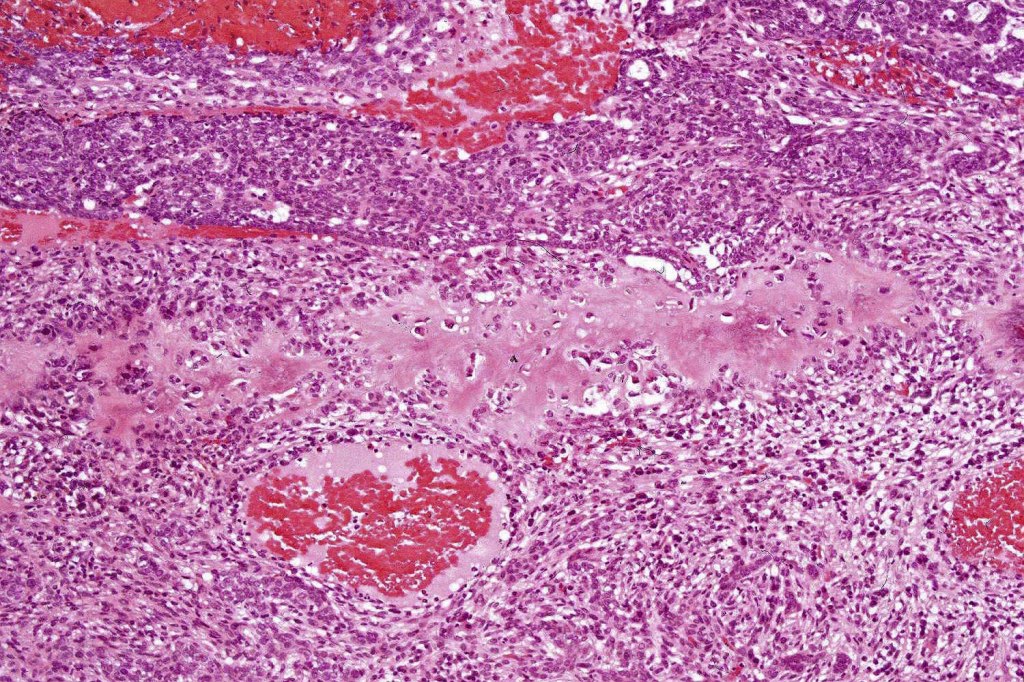

•Both epithelial & fibrous stromal components

•The tumor commonly arises from the epidermis

•Retraction artifact with stromal mucin

•Pseudoglandular appearance

. Perineural infiltration & lymphovascular invasion sometimes present